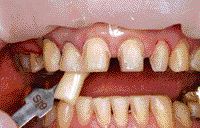

FIGURE 19--Preparations and shade taking.

Often patients present in our offices with aesthetic and functional problems which require addressing issues such as excessive overbite and insufficient posterior crown height. This case presentation will demonstrate treatment planning for a multiple disciplinary approach to the restoration of a dentition with reduced restorative dimension posteriorly, excessive overjet and severe overbite. Provisional laboratory processed … Read more